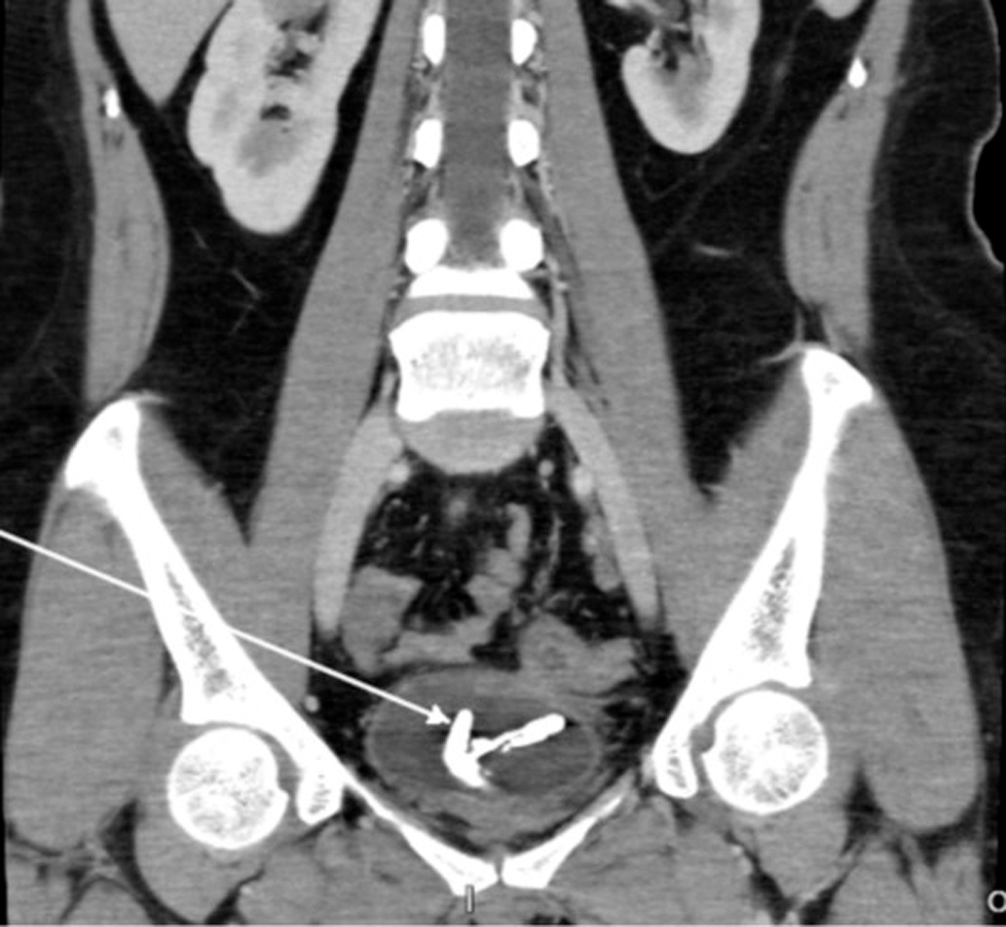

A 36-year-old woman presented with lower urinary tract obstruction symptoms. An abdominal CT scan revealed an encrustation of corpus alienum in the bladder, due to malposition of IUD copper T (Figure 1). The patient underwent cystoscopy + lithotripsy + IUD copper evacuation (Figure 2). Intraoperative findings revealed there was left posterolateral rectovesicula fistule. Clinically, no digestive remainders were found in the urine. CT scan examination also did not find any signs leading to rectovesicula fistule.

Figure 1. CT scan revealed an encrustation of IUD in the bladder.